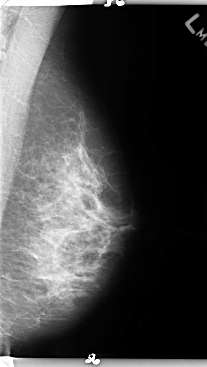

B_3156_1.LEFT_MLO

B_3156_1.LEFT_CC

LEFT_MLO LINES 4760 PIXELS_PER_LINE 2680 BITS_PER_PIXEL 12 RESOLUTION 50 NON_OVERLAY